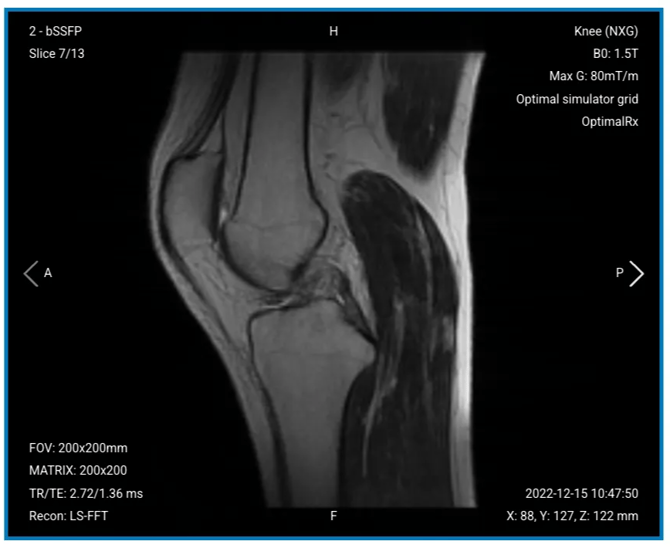

Each viewport contain information in the corners as follows:

Top-left corner

- Number of sequences run (e.g. 2, meaning the second sequence run)

- Name of sequence (e.g. bSSFP)

- Slice number over total number of slices in that series (e.g. Slice 7/13)

Top-right corner

- Model name (e.g. Knee (NXG))

- B0 strength (e.g. B0: 1.5T)

- Max gradient strength configuration (e.g. 80mT/m)

- Resolution of the model (e.g. optimal, which cannot be changed so it will always show this)

- Name of the selected coil (e.g. Optimal Rx)

Left-bottom corner

- FOV size (e.g. 200x200mm)

- Matrix size (e.g. 200x200)

- TR and TE values (e.g. 2.72/1.36ms)

- Reconstruction algorithm (e.g. LS-FFT)

Right-bottom corner

- Date and time of acquisition (e.g. 2022-12-15 10:47:50)

- Spatial coordinates (e.g. X: 88, Y:127, Z: 122mm)